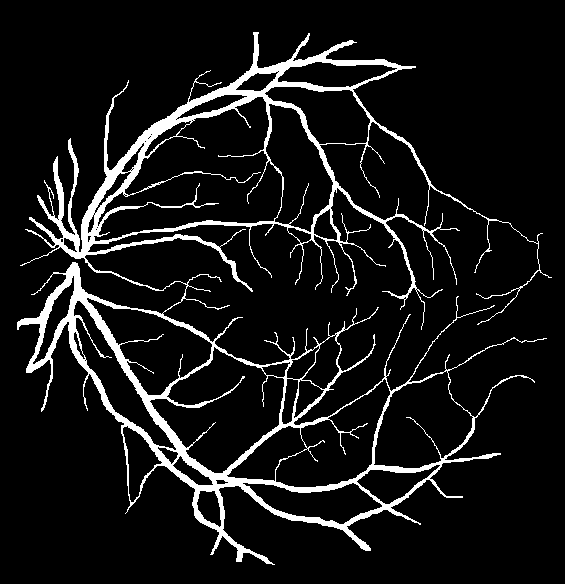

Refer to caption

(a) Original image

(b) Ground truth

(c) Binary mask

(d) Original image

(e) Ground truth

(f) Binary mask

Figure 7: Visual results for two sample DRIVE images.

Results for DRIVE Test Images: Quantitative results of BLCB-CNN for all DRIVE images are computed, which shows that the proposed method achieves an average accuracy of 96.22. The average sensitivity/specificity value of 81.57/97.65 also indicates the model’s ability to accurately segment vessel pixels (including thin vessels). The AUC results are also consistent with the accuracy obtained for all the images. Figure 7 demonstrates the visual outcomes for two sample DRIVE images. It can be observed that the proposed method segmented both thin and thick vessels much closer to ground truth binary masks. This is further evident from the focused rectangular areas of the output/ground-truth images.